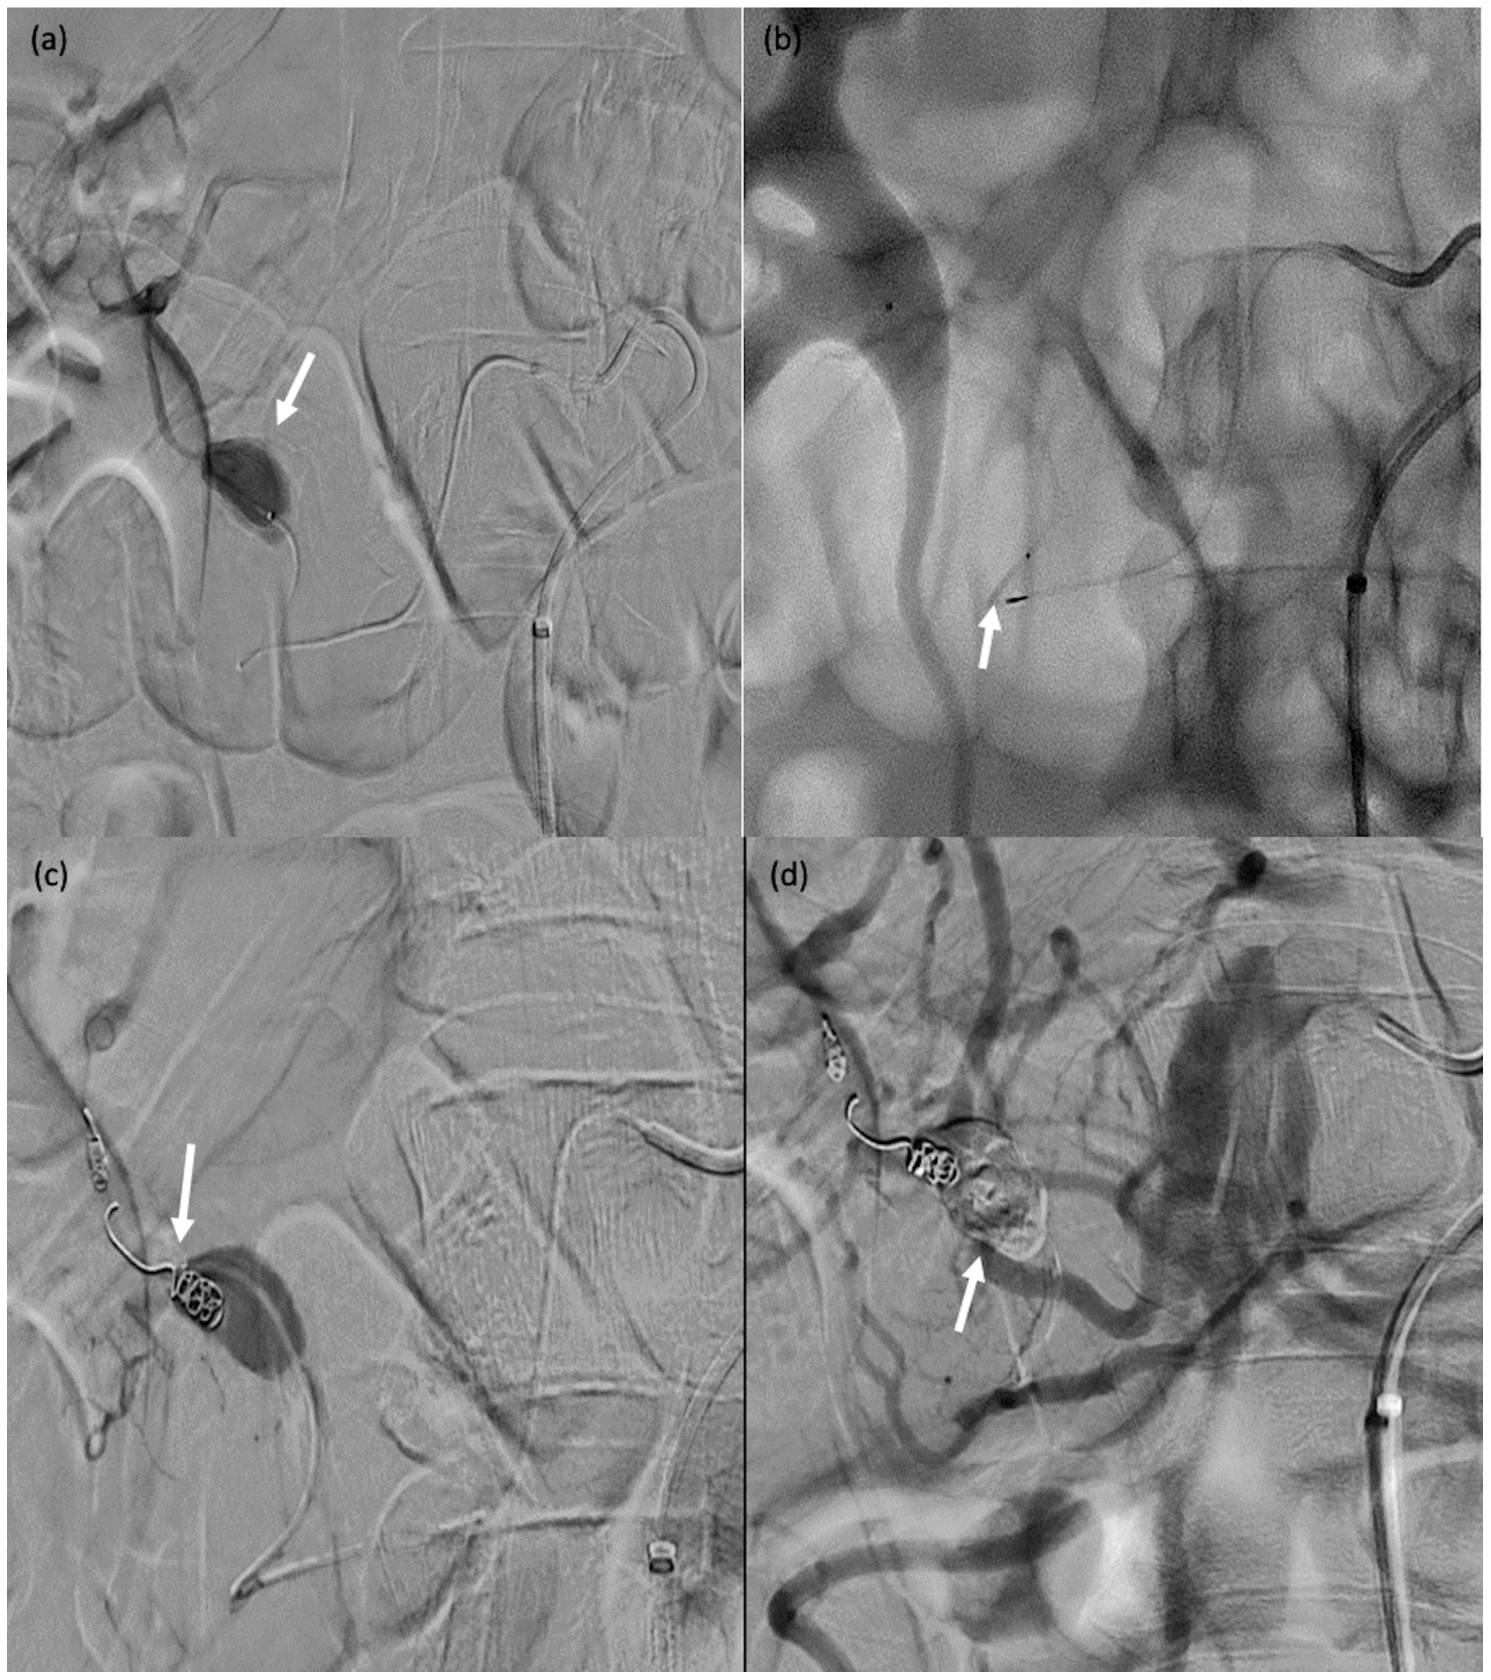

3.4. Technical Success Rate

Figure 6. A 32-year-old female patient (#13) who passed blood per rectum 2 days after a right partial nephrectomy; computed tomography showed active bleeding from the right colon; due to haemodynamic instability, she was transferred to the operating room for emergent angiography. (a) Angiography showing contrast agent extravasation at the right colon (arrow). (bd) Catheterisation of the target arterial branch was not feasible and a single MVP-3Q was therefore used for sandwich embolisation of the right arterial trunk at the appropriate level (arrows).

Figure 7. A 71-year-old male (patient #11) with abdominal pain and haemodynamic instability. (a) Rupture of a false aneurysm of the posterior pancreaticoduodenal arcade (arrow). (b) Failure of initial catheterisation for MVP-3Q implantation due to angulation of the target artery (arrow). (c) Coil embolisation of the downstream branch (arrow). (d) Onyx™ embolisation of the aneurysmal sac and upstream branch (arrow).